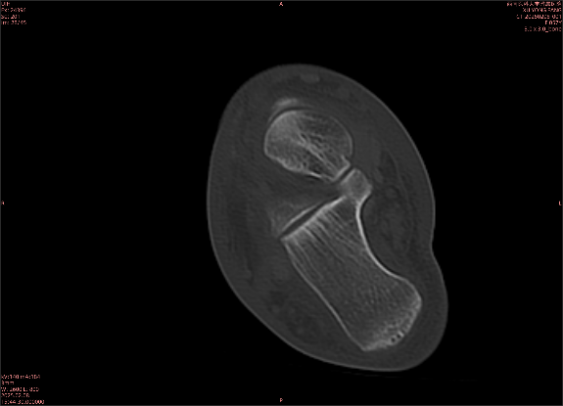

隱性骨折在MRI表現(xiàn)為T1WI序列上見由關(guān)節(jié)面向骨干走行的形態(tài)各異低信號(hào)區(qū),有線狀、條狀、紊亂低信號(hào),信號(hào)強(qiáng)度不均勻。與T1WI低信號(hào)改變相對(duì)應(yīng)部位在T2WI上表現(xiàn)為相應(yīng)形狀的高、低混雜信號(hào),且部分低信號(hào)周圍可見高信號(hào)水腫改變。STIR序列圖像上病灶呈顯著高信號(hào),與信號(hào)被抑制的臨近正常骨髓形成鮮明對(duì)比,分界也較T2WI成像更為清楚。脂肪組織抑制技術(shù)是MRI的一個(gè)重要性能,脂肪抑制技術(shù)在MRI應(yīng)用中可以改善組織對(duì)比和增加病變顯示機(jī)會(huì),這樣骨髓的脂肪抑制后就不會(huì)有任何信號(hào),而隱性骨折線及骨髓水腫的異常高信號(hào)就會(huì)更加明顯的顯示出來。

舉例圖像

圖1

專業(yè)解釋看不懂沒關(guān)系,大家看圖1和圖2就可以了,這是同一個(gè)患者跟骨的磁共振和CT圖像,圖1的紅色箭頭指示的黑線就是磁共振圖像顯示的骨折線,一目了然。而對(duì)比圖2的CT圖像上并未顯示異常。

這下大家明白了吧,如果懷疑隱匿性骨折優(yōu)先選擇磁共振檢查